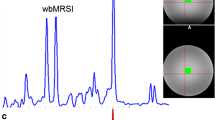

a Locations of each selected region of interest in the right brain hemisphere displayed as white filled circles on T2-weighted images of a 21-year-old healthy volunteer. The numbering represents the ROIs in the hand motor cortical area (1), postcentral gyrus (2), cingulate gyrus (3), splenium of the corpus callosum (4), thalamus (5), occipital area (6), temporal lobe lateral (7), temporal lobe medial (8), insular gyrus (9), hippocampus (10), cerebellum anterior lobe (11) and cerebellum posterior lobe (12). b Example metabolite maps of NAA, Cho, tCr, Glx, mI and spectral linewidth at the section level of the posterior cingulate gyrus with an example MR spectrum derived from wbMRSI. c Example tissue parameter maps of T2’, T1 and T2 at the section level of the posterior cingulate gyrus

Figure 1 shows the locations of selected regions of interest (ROI) in the right brain hemisphere, displayed as white filled circles or oval on the T2-weighted images of a 21-year-old female volunteer (Fig. 1a), the example tissue parameter maps and the metabolite maps at the section level of selected posterior cingulate gyrus ROI (Fig. 1b, c).